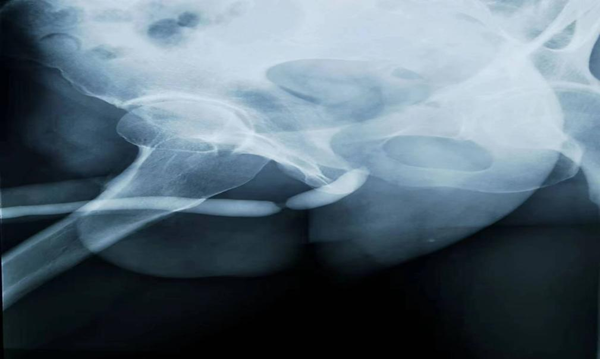

尿道逆行造影

泌尿外科主任顿金庚教授,副主任医师夏菲和李国军医疗团队接诊后,仔细询问病史,结合患者典型的外伤史、治疗史及术前尿道超声、顺行逆行造影片,明确患者为典型的尿道球部狭窄。结合患者较为年轻实际情况,考虑尿道球部端端吻合术可能对龟头的感觉及性功能的影响,经过科室讨论,特制定一套全新的手术方案,拟行“尿道球部狭窄非离断成形术”,完善术前相关检查,积极做好术前准备。

尿道超声

术前联合超声影像科副主任袁晓辉开展了尿道超声,对尿道狭窄部位、长度及瘢痕深度有了更精准的了解。本次手术根据患者尿道狭窄的位置,狭窄瘢痕严重情况及对性功能的要求情况,制定符合患者的最佳手术方式。尿道狭窄非离断成形术不但保障了尿道的连续性及血运循环,还不影响龟头的感觉,具有更微创,更符合生理及心理的康复,更有利于患者术后性功能恢复的优点。